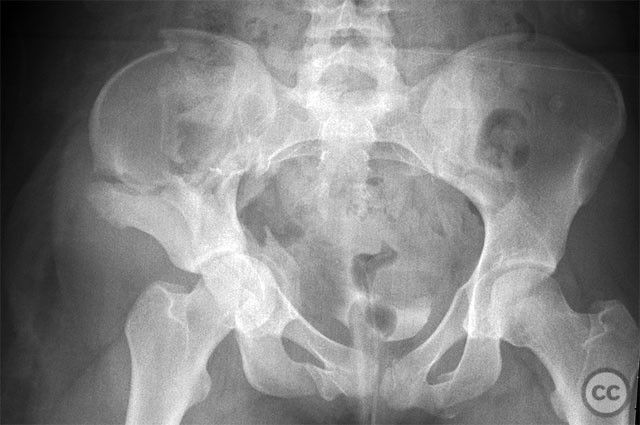

Clinical and radiological findings:  A 19-year-old female sustained a high-energy injury in a motor vehicle accident. Initial AP pelvic radiograph demonstrated a right-sided, displaced, comminuted associated both column acetabular fracture (AO/OTA 62C3), with a separate fracture fragment involving the greater sciatic notch (GSN). The right sacroiliac (SI) joint was incompletely disrupted. Surface rendered CT images confirmed the complex fracture morphology, including the separate GSN fragment and the SI-sacral injury, which rendered the typical posterior iliac fragment non-intact. Axial CT at the acetabular dome level revealed multiple displaced fragments and provided further detail regarding soft tissue involvement.